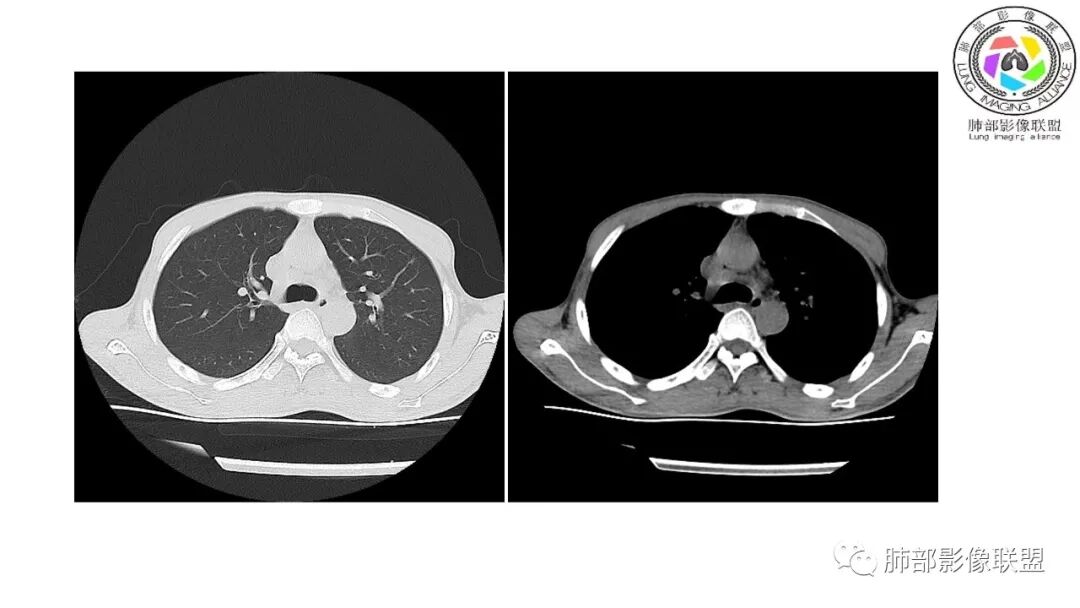

南边:12日好一些

南边:支持炎性,结合病史,马尼首选

影像与临床:1.青年男性,HlV阳性,颜面部皮疹(未提供皮疹图像)、发热(高热),实验室CRP、PCT高,T-Spot阴性。2.右肺下叶空洞结节,壁厚不均,边界清楚,其内线状影,未见液平及钙化,未见卫星灶,纵隔淋巴结增大,双侧腋窝见增大淋巴结。心腔内低密度提示贫血可能。肝脾影增大,未见结节影及块影。腹膜后见多发增大淋巴结。

综合分析:本例肺部影像学改变并不具有特征性,空洞性病灶须与多种疾病鉴别,但年轻HIV阳性患者,高热,皮疹,肝脾增大,纵隔、腋窝、腹膜后见多发增大淋巴结等都强烈提示马尔尼菲篮状菌感染的可能性。